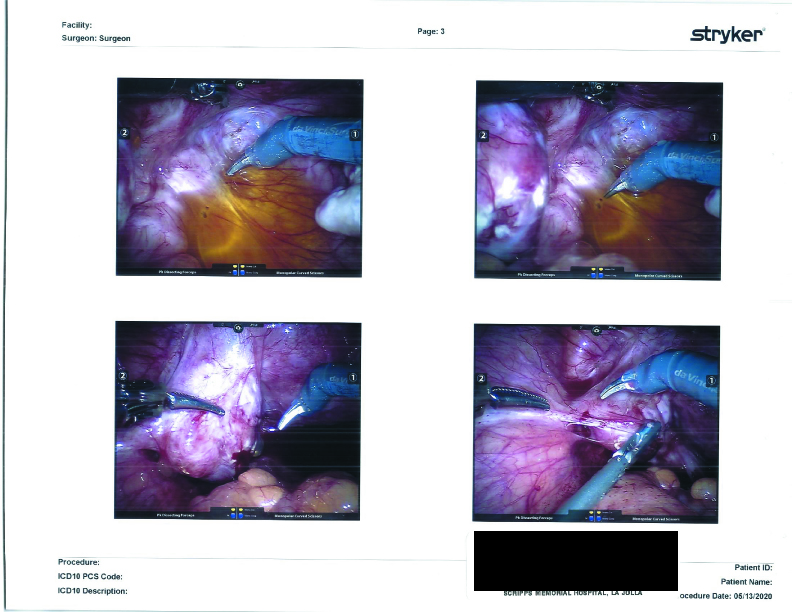

Not mentioned in the report, but is visible in the photographs and was discussed at my post-op meeting, was the yellow-tinged inflammatory fluid in my pelvis. It was at the bottom of my pelvis, just floating around as loose fluid. If you’ll recall a few months ago, my ultrasound technician found “loose fluid” in the area of my intestines. I was advised that this is “inflammatory fluid” and is normal to find in instances of leaking cysts, endometriosis, and adhesions. The fluid was removed during surgery.

Due to the closeness of the left ureter to the endometriosis lesions near my left ovarian fossa (the little cavity of the pelvis where an ovary sits) and the stuck left ovary against the pelvic wall, my surgeon took great care to keep the left ureter safe from any surgical damage. The left ovary and its cyst were completely removed. We had previously agreed to remove my left ovary due to ongoing pain and it proving to be a problem-child (for lack of a better term) discovered during previous surgeries.

Now, back to the guts. On my distal sigmoid colon, he found a patch of Endometriosis, which he notes as “a deep penetrating cluster of endometriosis lesion.” In my post-op appointment, he classified it as a nodule of Endometriosis, and said it looked like Deep Infiltrating Endometriosis to him. Unfortunately, due to the high risks involved in cutting that deeply into the intestine without a full bowel prep and a colo-rectal surgeon on hand, he took note (and photographs) of its positioning and opted not to remove the nodule. More on this will be addressed in “The Plan” section below.

Surgical Photographs

As promised here are the surgery photographs! Please be aware that the scans are low quality; the Endo on the colon is MUCH more visible, almost a dark purple blotch on the hard printouts. If I get higher-quality scans, I’ll be sure to update these. You can click on them for a larger image.